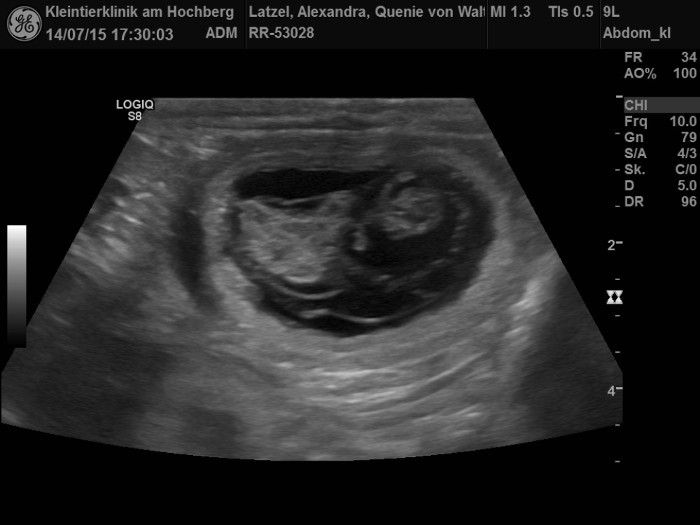

Aennchen war am 6. und 7. März zum Decken bei Homer. Aus dieser Verbindung gehen sechs Welpen hervor, wie das Ultraschallbild zeigt. |